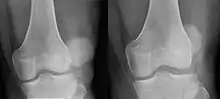

| Patellar luxation on radiograph: Left before, right after reduction; after reduction, the patella is still displaced. | |